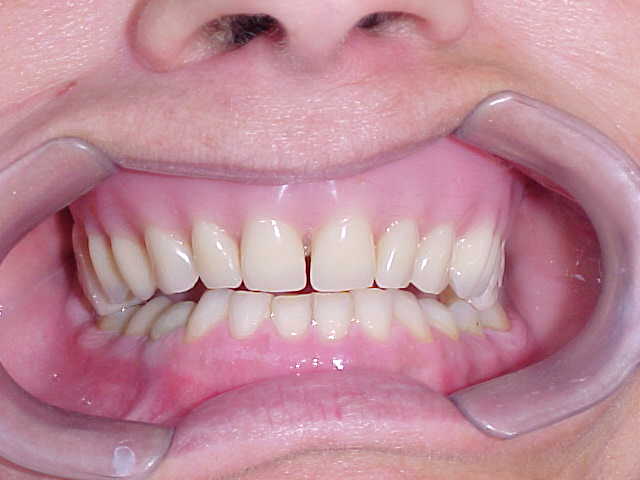

Vista frontal após correção ortodôntica e finalização da protocolo com dentes individuais em metalocerâmica

Em harmonia com os lábios

Total segurança ao sorrir

Nesta técnica, os dentes separados permitem o uso do fio dental em todos os espaços

Harmonia estética

Resultado final